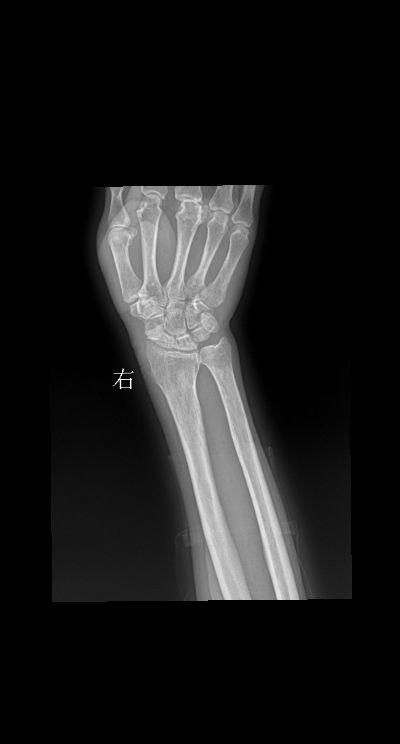

腕关节扭伤三天就诊 男 73y